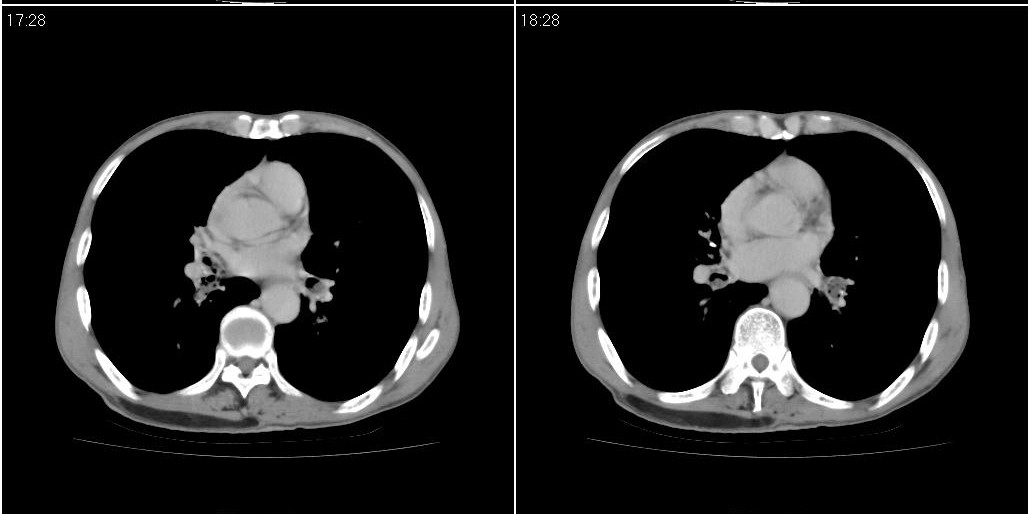

右肺中叶阻塞性不张及肺炎,高度怀疑支气管占位,建议纤支镜检查!

考虑右肺中叶感染。左肺下叶支扩。

右中肺阻塞性炎症,建议纤支镜!双下支扩感染。

1)右肺中叶慢性炎症并支气管扩张,节段性肺不张。2)两肺下叶支气管扩张。